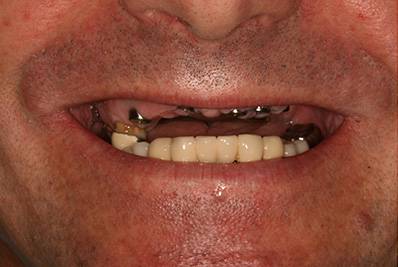

11. eset

27 éves páciensünk egész életében rettegett a fogorvosi beavatkozásoktól. Az összes foga elszuvasodott. A legkárosodottabb fogak gyökérkezelése és a szuvasodásainak megszűntetése után 26 fémkerámia koronát kapott a páciens. Erre a kezelésre is nagyon büszkék vagyunk. 2 hét leforgása alatt sikerült jelentős mértékben javítanunk a páciensünk mosolyán, önbizalmán és mióta velünk talalákozott, már a fogászati kezelésektől sem fél annyira!